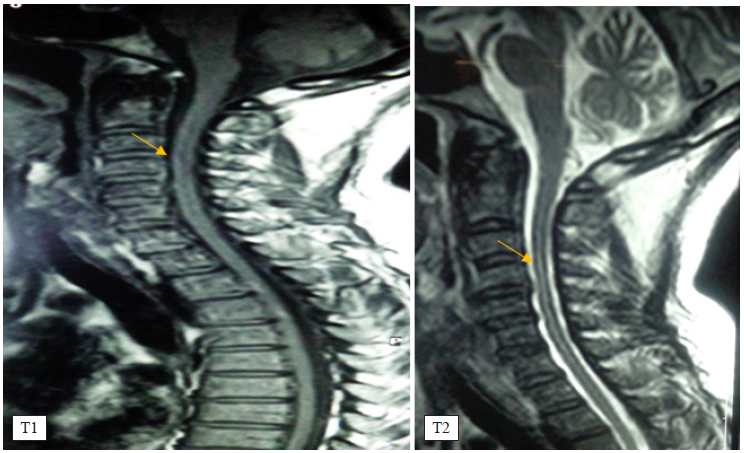

Para entonces la paciente no presentó artralgias ni signos inflamatorios en las articulaciones y su estado general era bueno. En junio del 2015, desarrolló en forma aguda, en un período de dos horas aproximadamente paraplejía fláccida, precedida de parestesias desde la región umbilical hasta la planta de los pies, de minutos de duración. Al examen neurológico se constató debilidad braquial moderada con definida paraplejía, acompañada de hiperreflexia y signos de Hoffmann y Babinski bilaterales. La exploración de la sensibilidad fue normal en todas sus formas. Internada en estas condiciones en el Departamento de Enfermedades Infecciosas y Tropicales del Hospital Dos de Mayo. Se conformó una junta médica quienes decidieron realizar biopsia de mucosa bucal y de un nódulo con eritema nudoso siendo reportado los hallazgos como indicativos de vasculitis linfocitaria, que permitió concluir con el diagnóstico de EB y mielopatía por vasculitis. Se efectuaron estudios en sangre y en el líquido cefalorraquídeo para descarte de enfermedad autoinmune frecuente en la mujer y mediante la reacción de cadena polimerasa (PCR) la infección por herpes, virus I-II y HTLVI-II. Los resultados analíticos fueron negativos. En el LCR los niveles de glucosa fueron normales, aumento de albúmina y pleocitosis linfocitaria. La prueba de patergia fue negativa. Finalmente, el estudio de neuroimágenes mediante la Resonancia Magnética de la médula espinal en T1 y en T2 mostraron mielopatía isquémica filiforme con extensión cervicodorsal (figura 6).

En la paciente mujer las manifestaciones neurológicas consistieron en el desarrollo agudo de enfermedad medular estratégica comprometiendo la región cervicodorsal en forma de una mielopatía de distribución longitudinal filiforme, afectando los tractos piramidales. Este compromiso neurológico se presentó después de siete años y fue precedida por las lesiones aftosas orales y genitales y el desarrollo de lesión correspondiente a eritema nodoso. De aquí se concluye que la mielitis tuvo un prolongado tiempo para presentarse, y de otro lado su recidiva al año y dos meses con las mismas características. Finalmente, durante todo el tiempo de la enfermedad no hubo manifestaciones neurológicas que indicaran compromiso del parénquima encefálico.

El compromiso de la médula espinal reportada en la literatura, como mielitis transversa multifocal, constituye una forma de mal pronóstico (6). En la presente investigación con seguimiento clínico de los pacientes, la mujer afectada desarrolló dos episodios de mielitis filiforme, con compromiso motor exclusivo, no encontrada en la literatura revisada.